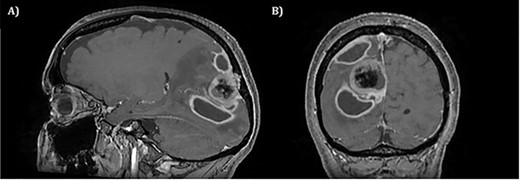

A 52-year-old female presented with headache and visual disturbance. She had no significant past medical history. On examination, a left homonomous inferior quadrantopia was noted. CT and then MRI imaging revealed a solitary 3-cm right parieto-occipital extra-axial lesion with associated dural tail and surrounding oedema (Fig. 1). Her headaches improved with a short course of steroids and the neuro-oncology MDT recommendation was for surgical excision of the suspected meningioma.

Axial view of a T1 weighted MRI post-gadolinium enhancement demonstrating the appearance of a 3-cm right parieto-occipital extra-axial mass with bony involvement and adjacent small nodule. Most in keeping with a meningioma.